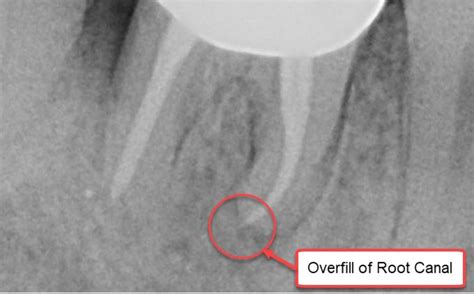

Once it is determined that a root canal is necessary, the procedure is surprisingly routine. The goal is to remove the source of the infection, sanitize the canals, and seal the tooth to prevent future bacteria from entering. First, a local anesthetic is administered to ensure comfort. A small opening is made in the crown of the tooth, and the infected pulp is carefully removed. The canals are then cleaned, shaped, and filled with a biocompatible material called gutta-percha. Finally, the tooth is typically restored with a crown to provide strength and protection against future fractures.